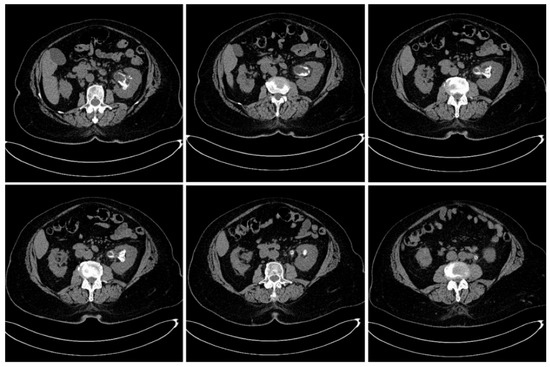

Emergency abdominal and pelvic non-contrast CT scan showed multiple thin left ureteral, pyelic, and calyceal calcifications on the surface of the urothelium, which are specific to encrusted uretero-pyelitis, with a maximum density of 510 Hounsfield units and with a mild dilation of the upper left urinary tract, right kidney hypoplasia, and enlarged retroperitoneal lymph nodes (Figure 1 and Figure 2).

Figure 1. Axial plane images of abdominal and pelvic CT scan without contrast showing multiple pyelic, calyceal, and ureteral calcifications specific to encrusted uretero-pyelitis.